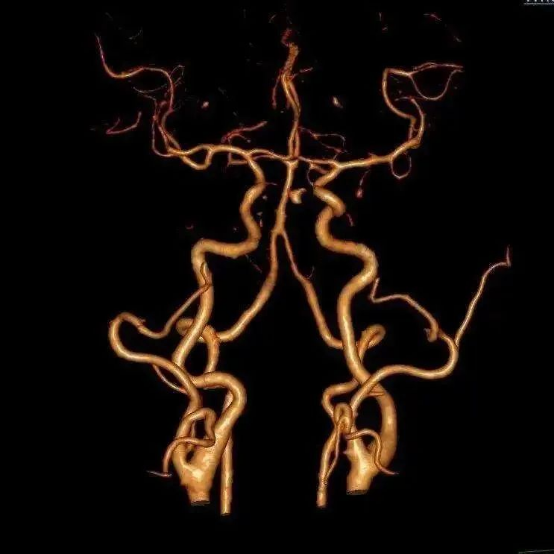

☆ CT血管成像(CTA)需注射含碘造影剂,在做之前需要了解肾功能情况(造影剂通过肾脏排泄),可以快速完成,病人痛苦少,分辨率较MRA有所提高,可以作为快速诊断脑血管疾病的方法及脑血管疾病的筛查。

☆ 全脑血管造影是最准确的脑血管造影方法,分辨率是最高的,是诊断脑血管疾病的“金标准”。在临床中,如果通过磁共振血管造影或CT血管造影检查,考虑有脑血管疾病的情况,特别是需要进一步治疗的时候,往往还是需要通过脑血管造影检查最后明确诊断,有些血管疾病在行脑血管造影检查的同时还可行介入治疗。